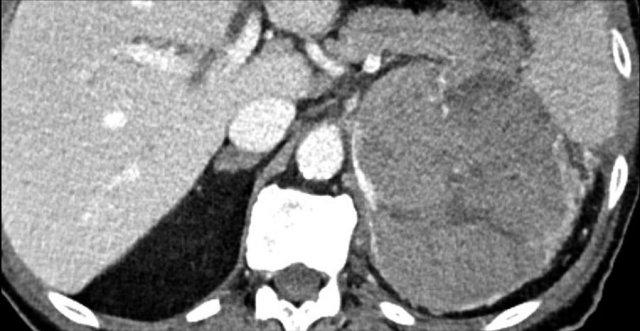

Các hình ảnh cho thấy u tình cờ tuyến thượng thận hai bên được phát hiện ở bệnh nhân 64 tuổi được chụp CT để phân tích phình động mạch chủ bụng.

Hình chụp pha động mạch cho thấy các tổn thương hai bên với tỷ trọng 50 HU.

Trên CT không tiêm thuốc thực hiện vài ngày sau, tỷ trọng ở cả hai tuyến thượng thận đều dưới 10 HU, xác nhận đây là các u tuyến giàu lipid.